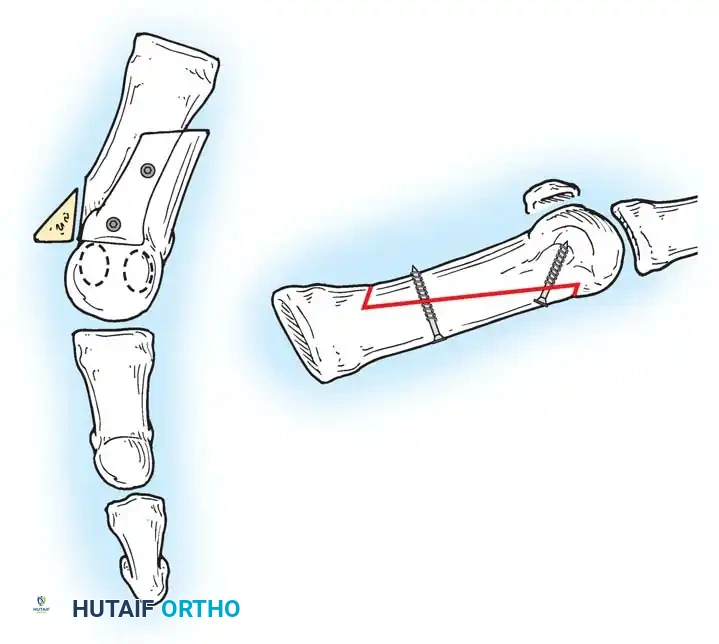

• Remove the base of the proximal phalanx at the metaphysealdiaphyseal junction, which usually constitutes the proximal third of the phalanx (Fig. 78-30A and B). To prevent damage to the fl exor hallucis longus and the neurovascular bundles, place a retractor over the bone dorsally and plantarward, and rotate the phalanx into view. Also, do not allow the saw blade to exit bone more than 1 to 2 mm.

• When the osteotomy has been completed, grasp the basilar fragment with a small Kocher clamp or towel clip, and rotate the fragment while applying medial pull to excise it. Lift it away from its lateral attachments, which are primarily the lateral collateral ligaments and the adductor muscle tendinous insertion (Fig. 78-30C).

• Grasp the hallux in one hand and displace the proximal remnant medially so that, under direct vision, two longitudinal 0.062-inch Kirschner wires can be inserted.

• Hold the interphalangeal joint straight while drilling the wires from proximal to distal, emerging a few millimeters plantar to the nail plate.

• Return the foot to the corrected position, and drill the wires into the metatarsal head.

• While holding the metatarsal as far laterally as possible, cross the joint, and drive the wires out the plantar cortex just proximal to the head, while holding the hallux in 10 to 15 degrees of extension, neutral abduction, adduction, and rotation, and no translation dorsally or plantarward on the metatarsal head. The wires should penetrate only 2 to 3 mm past the cortex to avoid tenderness over the wires with weight bearing.

• If the Kirschner wires tend to “walk” on the rounded articular surface of the metatarsal head, use a small hemostat snugged up against the wire while it is being drilled to allow accurate placement. Proper placement of the wires and the desired position of the hallux on the metatarsal may require several attempts. The medial aspect of the proximal phalanx should not rest medial to the medial aspect of the metatarsal head.

• Place the hallux in the neutral medial-lateral plane and in 10 degrees of extension.

• Before the second wire is driven into the fi rst metatarsal head, place the hallux in proper rotation, using the plane of the nail as a guide. The initial length of the hallux is maintained by the wires. Later, collapse occurs when the wires are removed, but improved encapsulation of the hemiarthroplasty, by maintaining length for the fi rst few weeks, may help maintain a more desirable position long-term.